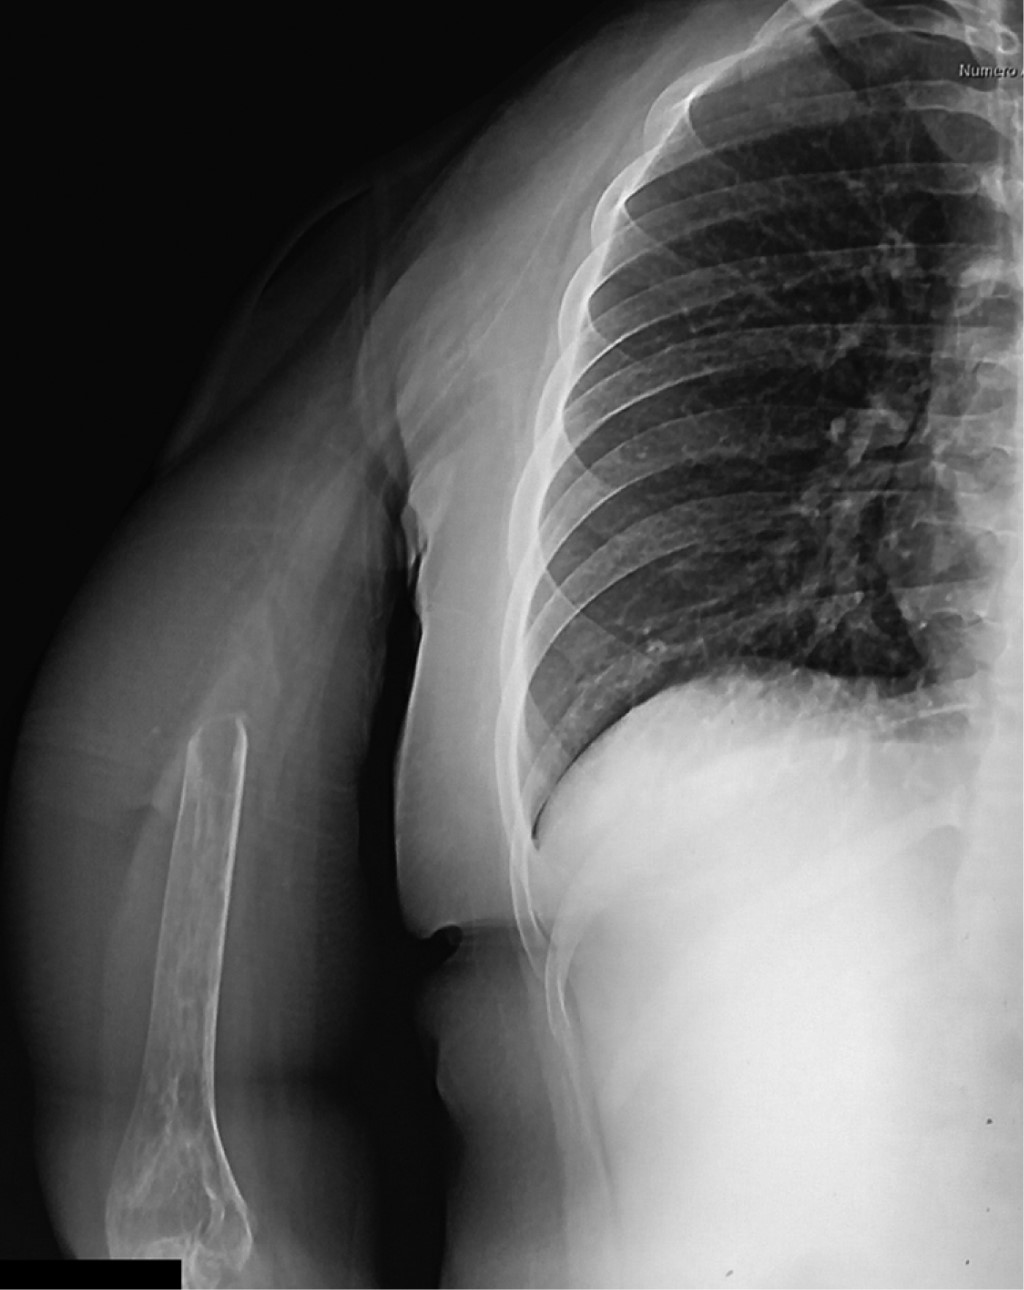

Paciente femenino de 17 años de edad, diestra, estudiante, que es enviada al Servicio de Ortopedia Pediátrica a consecuencia de tumor en el húmero proximal derecho. A simple vista se presenta importante aumento de volumen en el hombro derecho, así como limitación funcional principalmente a la abducción del hombro, así como parestesias distales. La función de hombro, muñeca y mano está conservada. Es difícil establecer el tiempo de evolución de la enfermedad, ya que existen contradicciones entre la versión de la paciente y la de sus padres; sin embargo, se considera que es de aproximadamente nueve meses, siendo su primera manifestación el aumento de volumen con progresiva disminución a la abducción. Esta lesión no había recibido tratamiento previo. Radiológicamente se trata de lesión osteolítica expansiva que muestra pérdida de la cortical y una sombra correspondiente a invasión neoplásica hacia los tejidos blandos circundantes (Figura 1). Tanto por tomografía como por resonancia magnética se observa el componente extracompartimental de la lesión, invasión articular y también a la escápula a expensas de permeación a la cortical anterior de la misma, así como gran desplazamiento medial de las estructuras neurovasculares, replegándolas hacia la parrilla costal (Figura 2). Una vez realizados estudio y análisis clínico e imagenológico, se realiza biopsia, la cual reporta tumor óseo de células gigantes. Se discute el caso y se llega a la conclusión de que la mejor alternativa terapéutica es una resección extraarticular de escápula con inclusión de más de la mitad proximal del húmero derechos. Previo al procedimiento quirúrgico se les informa detalladamente a los padres y a la paciente sobre el mismo, quienes lo autorizan. Dicho procedimiento se cataloga como resección tipo VI B de Malawer. El acto quirúrgico se llevó a cabo sin complicaciones, comentando que el grupo muscular de flexores del codo precisó de su resección en su mitad proximal, por lo que el remanente distal se reinsertó sobre la delgada fascia anterior del brazo (Figuras 3 y 4). Se inmovilizó la extremidad superior de la paciente por tres semanas y posteriormente se inició programa para reinicio de la función de la extremidad dentro de los rangos que la resección realizada permitió. A tres meses del evento quirúrgico, la función obtenida se estableció como 25/30 basados en el MSTS score (Figura 5). A los seis meses de vigilancia postoperatoria, por medio de tomografía computada, se detectó una lesión compatible con metástasis única pulmonar basal en el hemitórax derecho. Se revisaron estudios preoperatorios, no encontrándose indicio de que se tratara de una lesión ya existente al diagnóstico. Se solicitó valoración por cirugía oncológica, quienes determinan la realización de una minitoracotomía para realizar la metastatectomía correspondiente; se confirmó sospecha diagnóstica.

Figura 1